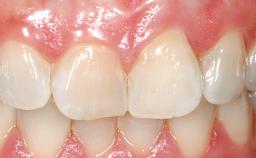

This 43-year-old male patient, a non-smoker, came to our practice because of a fracture of tooth 12 caused by a bicycle accident. Due to the combined para- and infrabony crown and root fracture, tooth extraction, and subsequent implant placement were suggested to the patient as the therapy of choice. The patient had high esthetic expectations with regard to the treatment outcome and asked for an immediate fixed provisional restoration. His individual esthetic risk profile summed up to a medium esthetic risk.